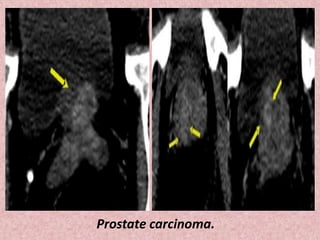

Prostate carcinoma.